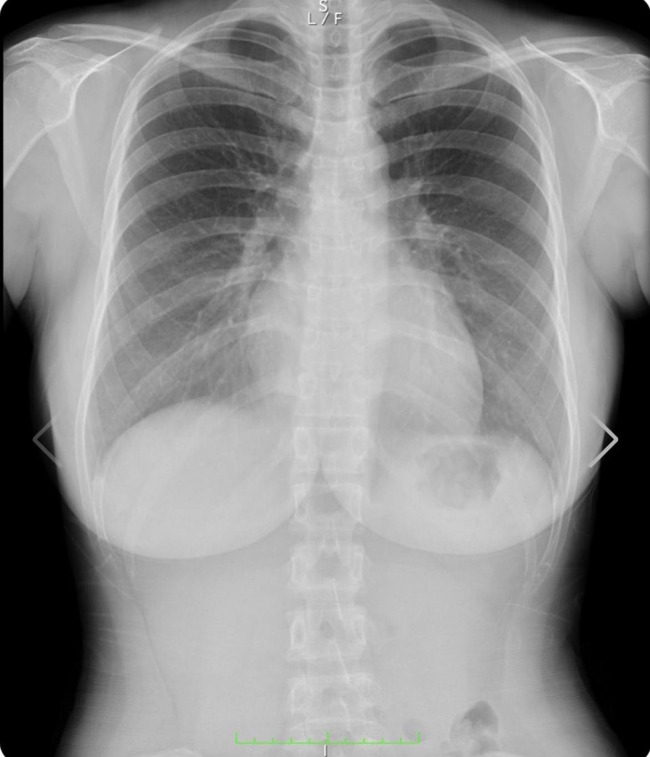

デカい乳癌やん

ステージ3やな

綺麗な肺やね。

健康そのものや

少し背骨曲がってない?